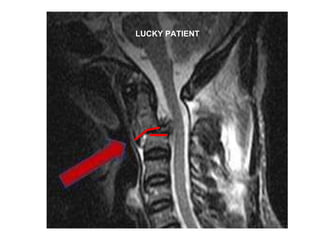

LUCKY PATIENT

Results  MRI scans in all patients Early operation in majority No intra-operative complications Safe operations with minimum equipment 2 patients were irreducible

Irreducible dislocation but cord well decompressed